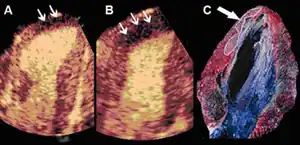

Infarct size determination

Adenosine infusion, can increase perfusional defect, as a result per an animal study indicates that "a better correlation between the echocardiographic measurements and the necrotic area determined by tissue staining". [39]